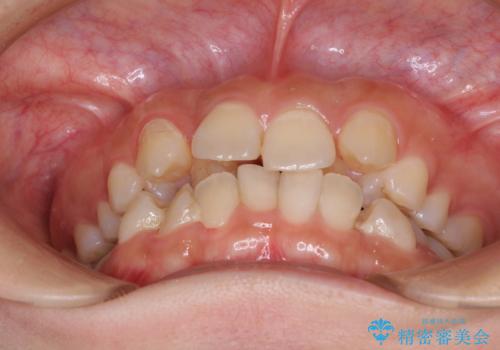

見えないほど重なっている前歯 抜歯矯正でスッキリとした歯並びに

- 前歯の著しいデコボコを気にして来院された患者様です。

上顎の左右側切歯(前から2番目)が裏側に隠れいてる状態で、咬み合わせや清掃性に大きな問題が認められました。

左下に八重歯があったそうですが、当時は矯正治療を行うことを考えていなかったため、抜歯してしまったとのことでした。

叢生が著しいため、左下以外の第一小臼歯3本を抜去し、目立たないワイヤー装置にて矯正治療を行うこととしました。